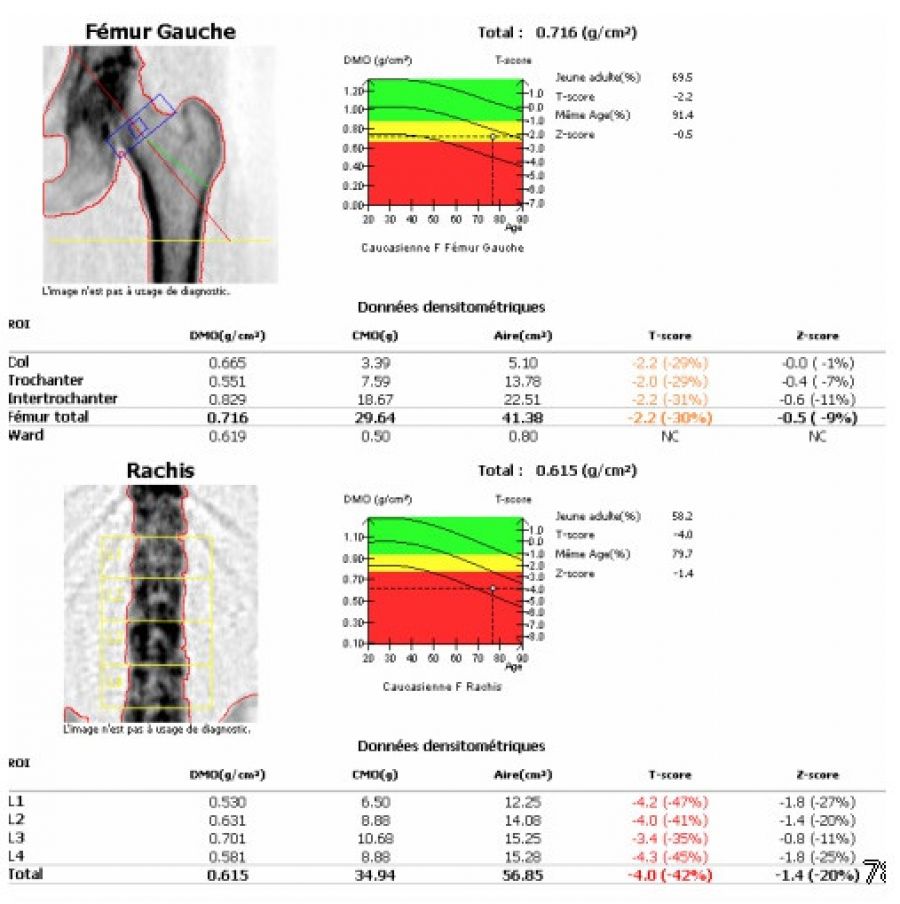

C'est un examen radiologique qui permet un diagnostic précoce de l'ostéoporose ainsi qu'une évaluation du risque fracturaire, ce qui permet de  metre en oeuvre un traitement et une prévention.

L'ostéodensitométrie biphotonique ou DXA est la technique de référence pour mesurer la déminéralisation appelée DMO par rapport au capital osseux initial. Elle permet aussi de surveiller un traitement de l'ostéoporose.

Un indice, le T-score pour caractériser votre bilan osseux